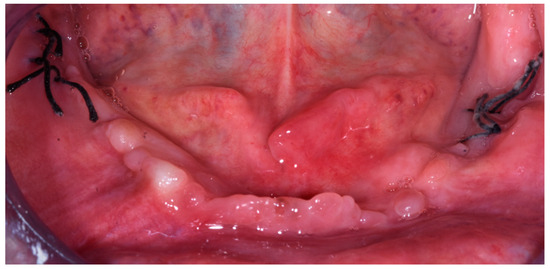

- Platelet-Rich Growth Factors (PRGF) were inserted in the residual empty area left from the explantation of the nails and of the related infections.

2.1.1. Surgery Appointment (September 2021)

2.1.3. Follow Ups and Implants Insertion